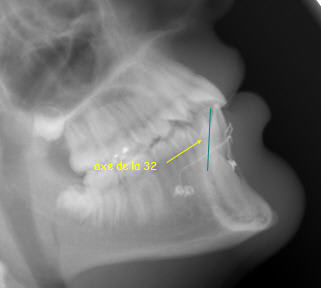

Sur ce cliché, les couronnes sont à autre niveau par rapport à la verticale et pourtant c’est toujours le même cas…

Quand je vais chercher une canine incluse pour la tracter, ce qui m’importe c’est l’endroit ou je vais la trouver en dégageant le moins possible. J’avais ouvert ici en vestibulaire et sa couronne n’était recouverte que d’une fine pellicule osseuse de l’épaisseur d’un papier à cigarette. On aurait pu discuter si j’avais dû fraiser profondément, mais ça n’a pas été le cas.

lorsque l'on prend un panoramique le patient se tient debout

la verticale est donc la verticale du patient (a peu de chose pres), le bord des incisives dans la fourchette de de la pano

et non pas tete completement penché en arriere comme tu le simules en faisant une rotation de l'image

car le referentiel c'est la relation de position entre le tube panoramique et la position du patient dans la machine

ainsi le patient est debout et la zone de tomographie est la zone verte comme situé sur mon image (remise dans les conditions reelles de prise du cliché)

par consequent, MOI je dis que la couronne de la canine est situé en arriere de la couronne des incisives mandibulaires ( par rapport à la verticale comme defini precedement) ce que qui fait que la règle enoncé au debut reste juste